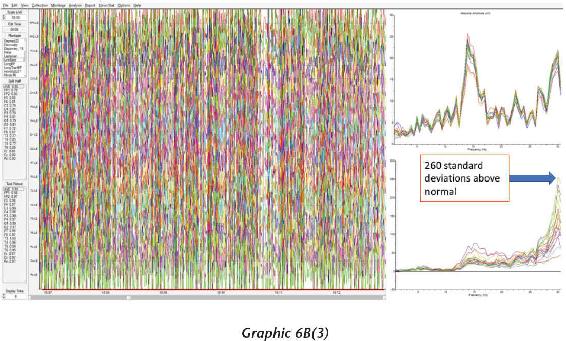

We have thousands and thousands of brain scans that prove those changes were not just imagined in their minds but actually took place in their brains. Several of the students we measured accomplished those changes within four days (the length of our advanced workshops). The scientific teams I’ve assembled have taken brain scan recordings using quantitative electroencephalogram (EEG) measurements before and after workshops as well as real-time measurements during the meditations and practices themselves. I was not only impressed with the changes, but shocked by them—they were that dramatic.

At the end of 2013, something mysterious started occurring. We started seeing brain scan recordings that puzzled the researchers and neuroscientists who came to our events to study my work. The high amount of energy in the brain that we were recording while a student was in certain meditations had never been recorded up until this point. And yet we were seeing these off-the-charts readings again and again.

When we interviewed the participants, they reported that their subjective experience during the meditation was very real and mystical, and that this either profoundly changed their view of the world or dramatically improved their health. I knew in those moments that these participants were having transcendental experiences in their inner world of meditation that were more real than anything they had ever experienced in their outer world. And we were capturing those subjective experiences objectively.

That has become a new normal for us now, and as a matter of fact, we can often predict when these high amplitudes of energy in the brain will occur, based on certain indicators and signs that we have seen for years now. In these pages, I want to demystify what it is to have an interdimensional experience as well as provide the science, biology, and chemistry of the organs, systems, and neurotransmitters that make this happen. It is my hope that this information will give you a road map for how to create such experiences for yourself.